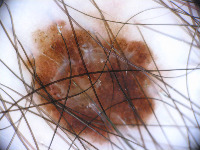

Dermatology Research: Researchers studying skin conditions could use this model to detect changes in the skin color, texture, or other characteristics over time. The model could help identify early signs of skin diseases and track their progression or regression.